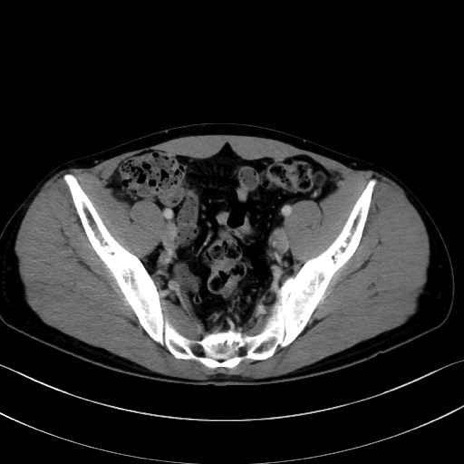

2. 腸腰筋群と骨盤底筋

大腰筋 (Psoas major)

腸骨筋 (Iliacus)